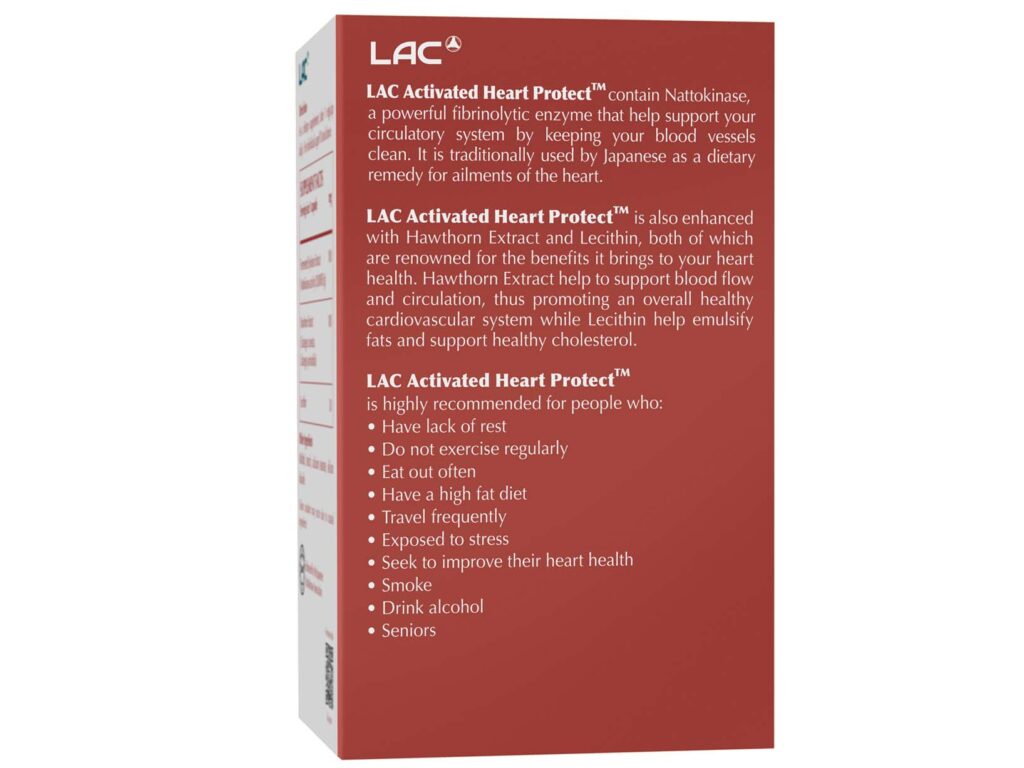

BOOST YOUR HEART HEALTH WITH

LAC ACTIVATED HEART PROTECT™